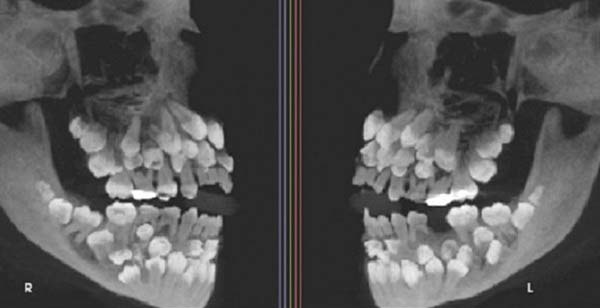

브라질의 한 11세 소녀 입안에서 무려 81개의 치아가 발견돼 학계의 주목을 받고 있다. 일반적인 치아 개수는 32개다.

17일(현지시각) 베트남 VN익스프레스 등 외신에 따르면, 브라질 미나스제라이스주에 사는 소녀는 유치 한 개를 빼기 위해 병원을 찾았다가 엑스레이 검사 중 총 81개의 치아가 있다는 사실이 확인됐다. 유치 18개, 영구치 32개, 과잉치 31개였다. 소녀를 진료한 주이스지포라 연방대 치과병원 연구진은 “이런 상태는 ‘다발성 과잉치증’”이라며 “보통은 한두 개의 과잉치만 생기는데, 30개 이상 발견된 사례는 전 세계적으로도 매우 드물다”고 말했다.

치아 수가 지나치게 많다 보니 치료에도 어려움이 있었다. 일부 과잉치는 잇몸 깊숙이 묻혀 있거나 정상 치아와 형태가 비슷해 구분이 어렵고, 무리하게 제거할 경우 턱뼈 손상의 우려도 있었다. 이에 따라 연구팀은 “교정과, 악안면외과, 치주과, 보철과 등 여러 전문과가 협력하는 협진 체계를 마련해 장기적인 치료 계획을 수립했다”고 말했다.